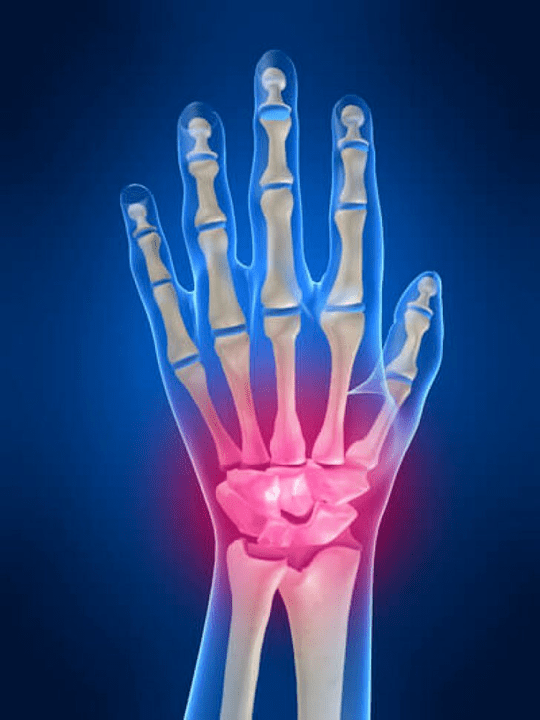

L'articulation du poignet

L'articulation du poignet est formée par les os des os proximaux (supérieur) un certain nombre de poignets (Trièdre, croissant de lune, os scaphoïdes) et les zones distales de rayonnement et d'os des coudes. L'os du coude n'est pas directement connecté aux os du poignet, mais à l'aide de distal (Inférieur) Le disque conjoint. Cette structure sépare la cavité de l'articulation du poignet de la cavité distale (Inférieur) L'articulation des carreaux.